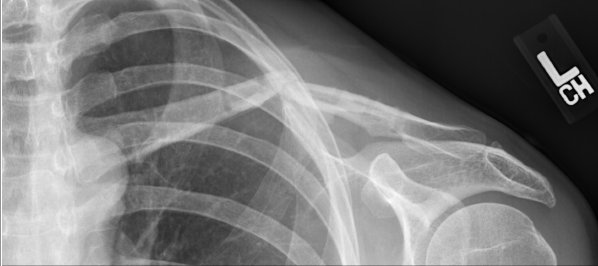

- Broken left collar bone after falling off my bike. (bridge over Adobe Creek on East Bayshore Rd)

The bone was too badly shattered to allow natural healing, so I had a metal plate inserted 10 days after the break, with bone putty to try to guide and speed up bone regeneration. The screws holding the plate backed out and abraded inside of skin, so the same doctor removed the plate after 6 months. The bone broke again 6 days later under light use. A new surgeon worked to fix it by running a threaded rod put down the center of the bone, held in position by a "nut" that sticks out of the back of the shoulder joint. (This is a fairly new procedure and has only been in general use for 1-2 years.) That pin pierced the collarbone and wound up sticking out the front of the bone, threatening to puncture the skin and creating a "teeter-totter" effect for the two halves of my collarbone (preventing rejoining). The surgeon went back again, removed the original pin, and rethreaded a new, longer pin down the back of the two halves of the bone. So far, this seems to be working well (fingers crossed). I will need to go back for more surgery in 12-24 months to have the pin removed.